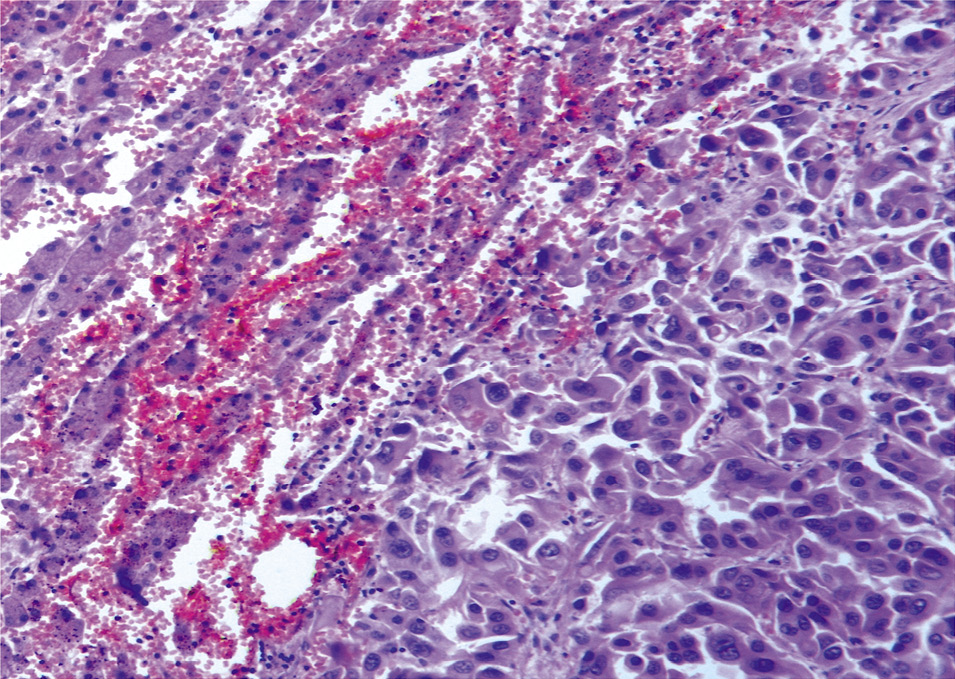

При секционном исследовании определяются признаки, характерные для периферического рака правого легкого с множественными метастазами по всем полям легких, в печень, селезенку, поджелудочную железу, с отсутствием метастазов в лимфатические узлы. При макроскопическом исследовании структура легких просматривается с трудом из-за выраженного диссеминированного наличия серых плотноватых узлов в диаметре от 0,2 до 0,9 см, местами сливающихся. В области средней доли правого легкого определяется опухолевая ткань с выраженным слиянием и тенденцией формирования конгломерата, распространяясь к долевому бронху, без сужения просвета. При гистологическом исследовании отмечаются обширные участки формирования опухолевой ткани, состоящей из солидных структур с железистой дифференцировкой опухолевой ткани разной величины и формы, выстланные крупными приз- матическими клетками с округлыми и овальными базально расположенными ядрами, цитоплазма которых хорошо выражена. Отмечается выраженный полиморфизм клеток с большим числом патологических митозов (рис. 1, 2). В просвете сегментарных и мелких ветвей легочной артерии – свертки крови, тромбы в диаметре от 0,2 до 0,7 см, длиной до 3,0 см, выдавливающиеся в виде «червячков» (рис. 3).

Рис. 2. Микроскопическая картина опухолевой ткани, образующей железистые структуры с полиморфными атипичными клетками и патологическими митозами, с опухолевыми эмболами в сосудах, встречаются клетки по типу перстневидных. Окраска гематоксилином и эозином, ×900.